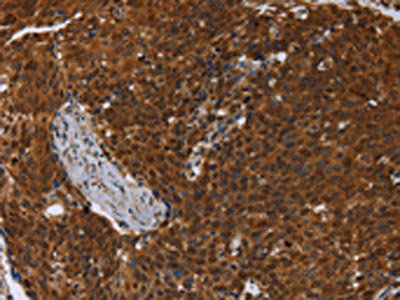

The image on the left is immunohistochemistry of paraffin-embedded Human ovarian cancer tissue using CSB-PA132314(MCHR1 Antibody) at dilution 1/30, on the right is treated with synthetic peptide. (Original magnification: ×200)

The image on the left is immunohistochemistry of paraffin-embedded Human cervical cancer tissue using CSB-PA132314(MCHR1 Antibody) at dilution 1/30, on the right is treated with synthetic peptide. (Original magnification: ×200)